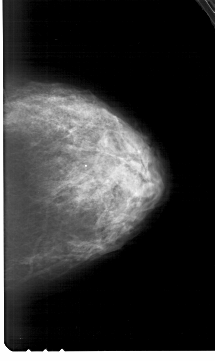

A_1983_1.LEFT_CC

LEFT_CC LINES 6436 PIXELS_PER_LINE 3811 BITS_PER_PIXEL 12 RESOLUTION 43.5 OVERLAY